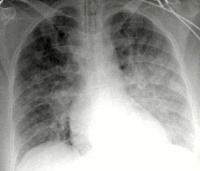

ЭКГ показывает признаки пароксизмальных расстройств, острого коронарного синдрома, ишемии миокарда (коронарная волна, повышение сегмента ST). Дифракция рентгеновских лучей указывает на уменьшение пневматизации полей легких, таких как метель, при альвеолярном разнообразии видна затемнение в форме бабочки. УЗИ сердца определяет признаки гипокинезии левого желудочка.